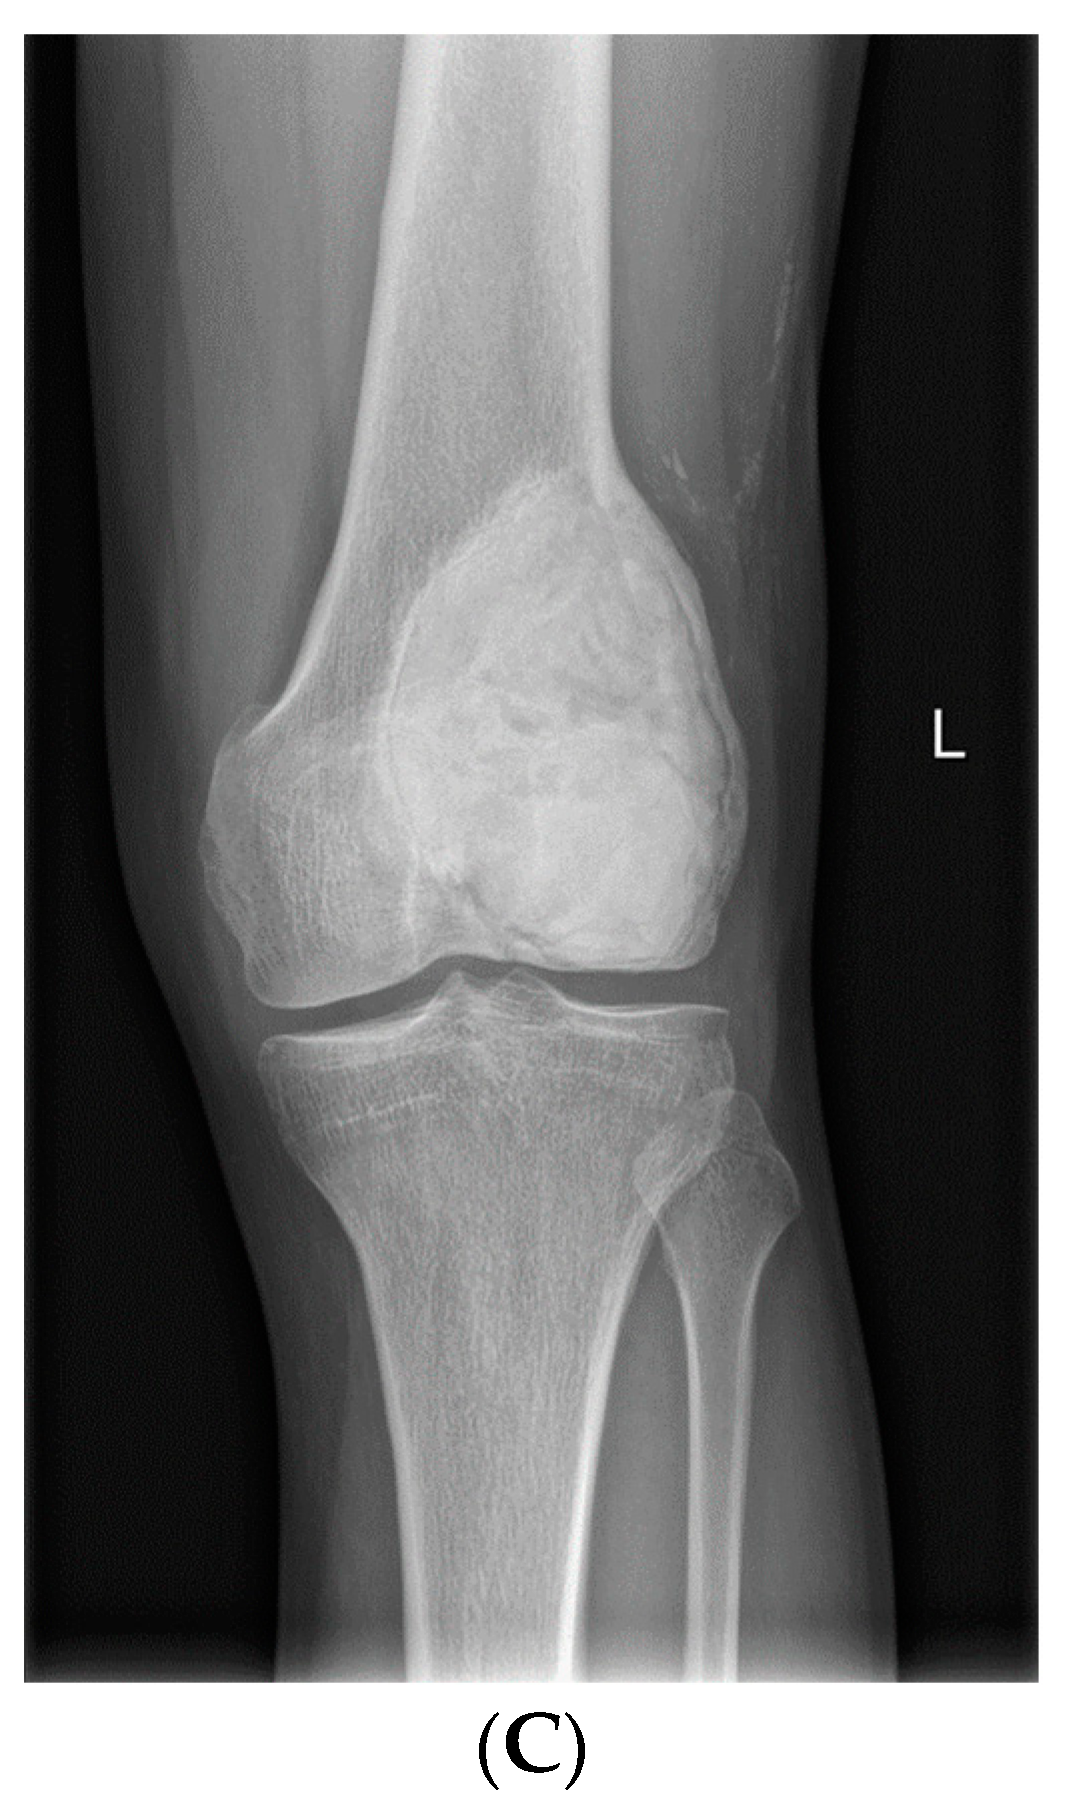

- Van Langevelde, K.; McCarthy, C.L. Radiological findings of denosumab treatment for giant cell tumours of bone. Skelet. Radiol. 2020, 49, 1345–1358. [Google Scholar] [CrossRef] [PubMed]

- Murphey, M.D.; Nomikos, G.C.; Flemming, D.J.; Gannon, F.H.; Temple, H.T.; Kransdorf, M.J. Imaging of Giant Cell Tumor and Giant Cell Reparative Granuloma of Bone: Radiologic-Pathologic Correlation. RadioGraphics 2001, 21, 1283–1309. [Google Scholar] [CrossRef]

- Oguro, S.; Okuda, S.; Sugiura, H.; Matsumoto, S.; Sasaki, A.; Susa, M.; Morioka, H.; Jinzaki, M. Giant Cell Tumors of the Bone: Changes in Image Features after Denosumab Administration. Magn. Reson. Med. Sci. 2018, 17, 325–330. [Google Scholar] [CrossRef]

- Hakozaki, M.; Tajino, T.; Yamada, H.; Hasegawa, O.; Tasaki, K.; Watanabe, K.; Konno, S. Radiological and pathological characteristics of giant cell tumor of bone treated with denosumab. Diagn. Pathol. 2014, 9, 111. [Google Scholar] [CrossRef]

- Veng, C.; Jørgensen, P.H.; Krog-Mikkelsen, I.; Stilling, M. Measurement of bone mineral density as an efficacy marker in denosumab treatment of giant cell tumour of bone. BMJ Case Rep. 2017, 2017, bcr2017220369. [Google Scholar] [CrossRef] [PubMed]